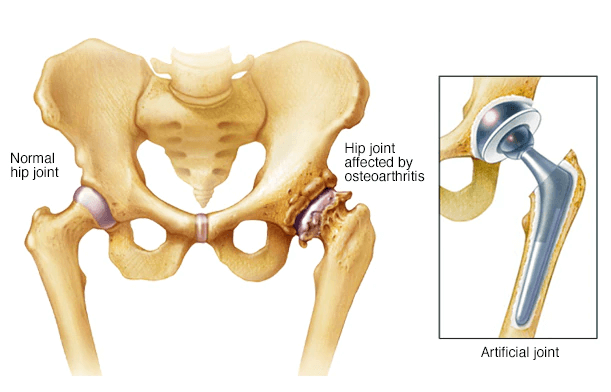

Total Hip Replacement

The Hip The hip joint is located where the upper end of the femur meets the acetabulum. The femur (thigh bone) looks like a long stem with a ball on[…]

Robotic Hip and Knee Replacement

An advanced surgical procedure that uses robotic-assisted technology to enhance precision, improve implant positioning, and optimize patient outcomes